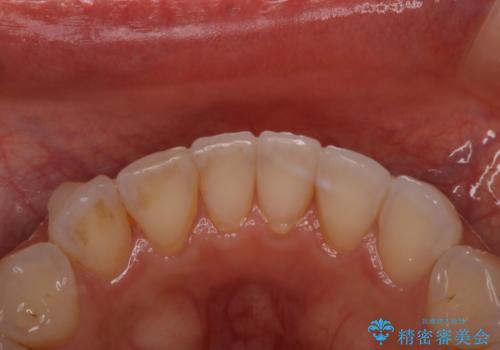

マウスピース矯正(インビザライン)中のPMTC

- インビザラインでの矯正治療中の方です。久しぶりにクリーニングをしたいとのことでした。

PMTC60分コースを行いました。